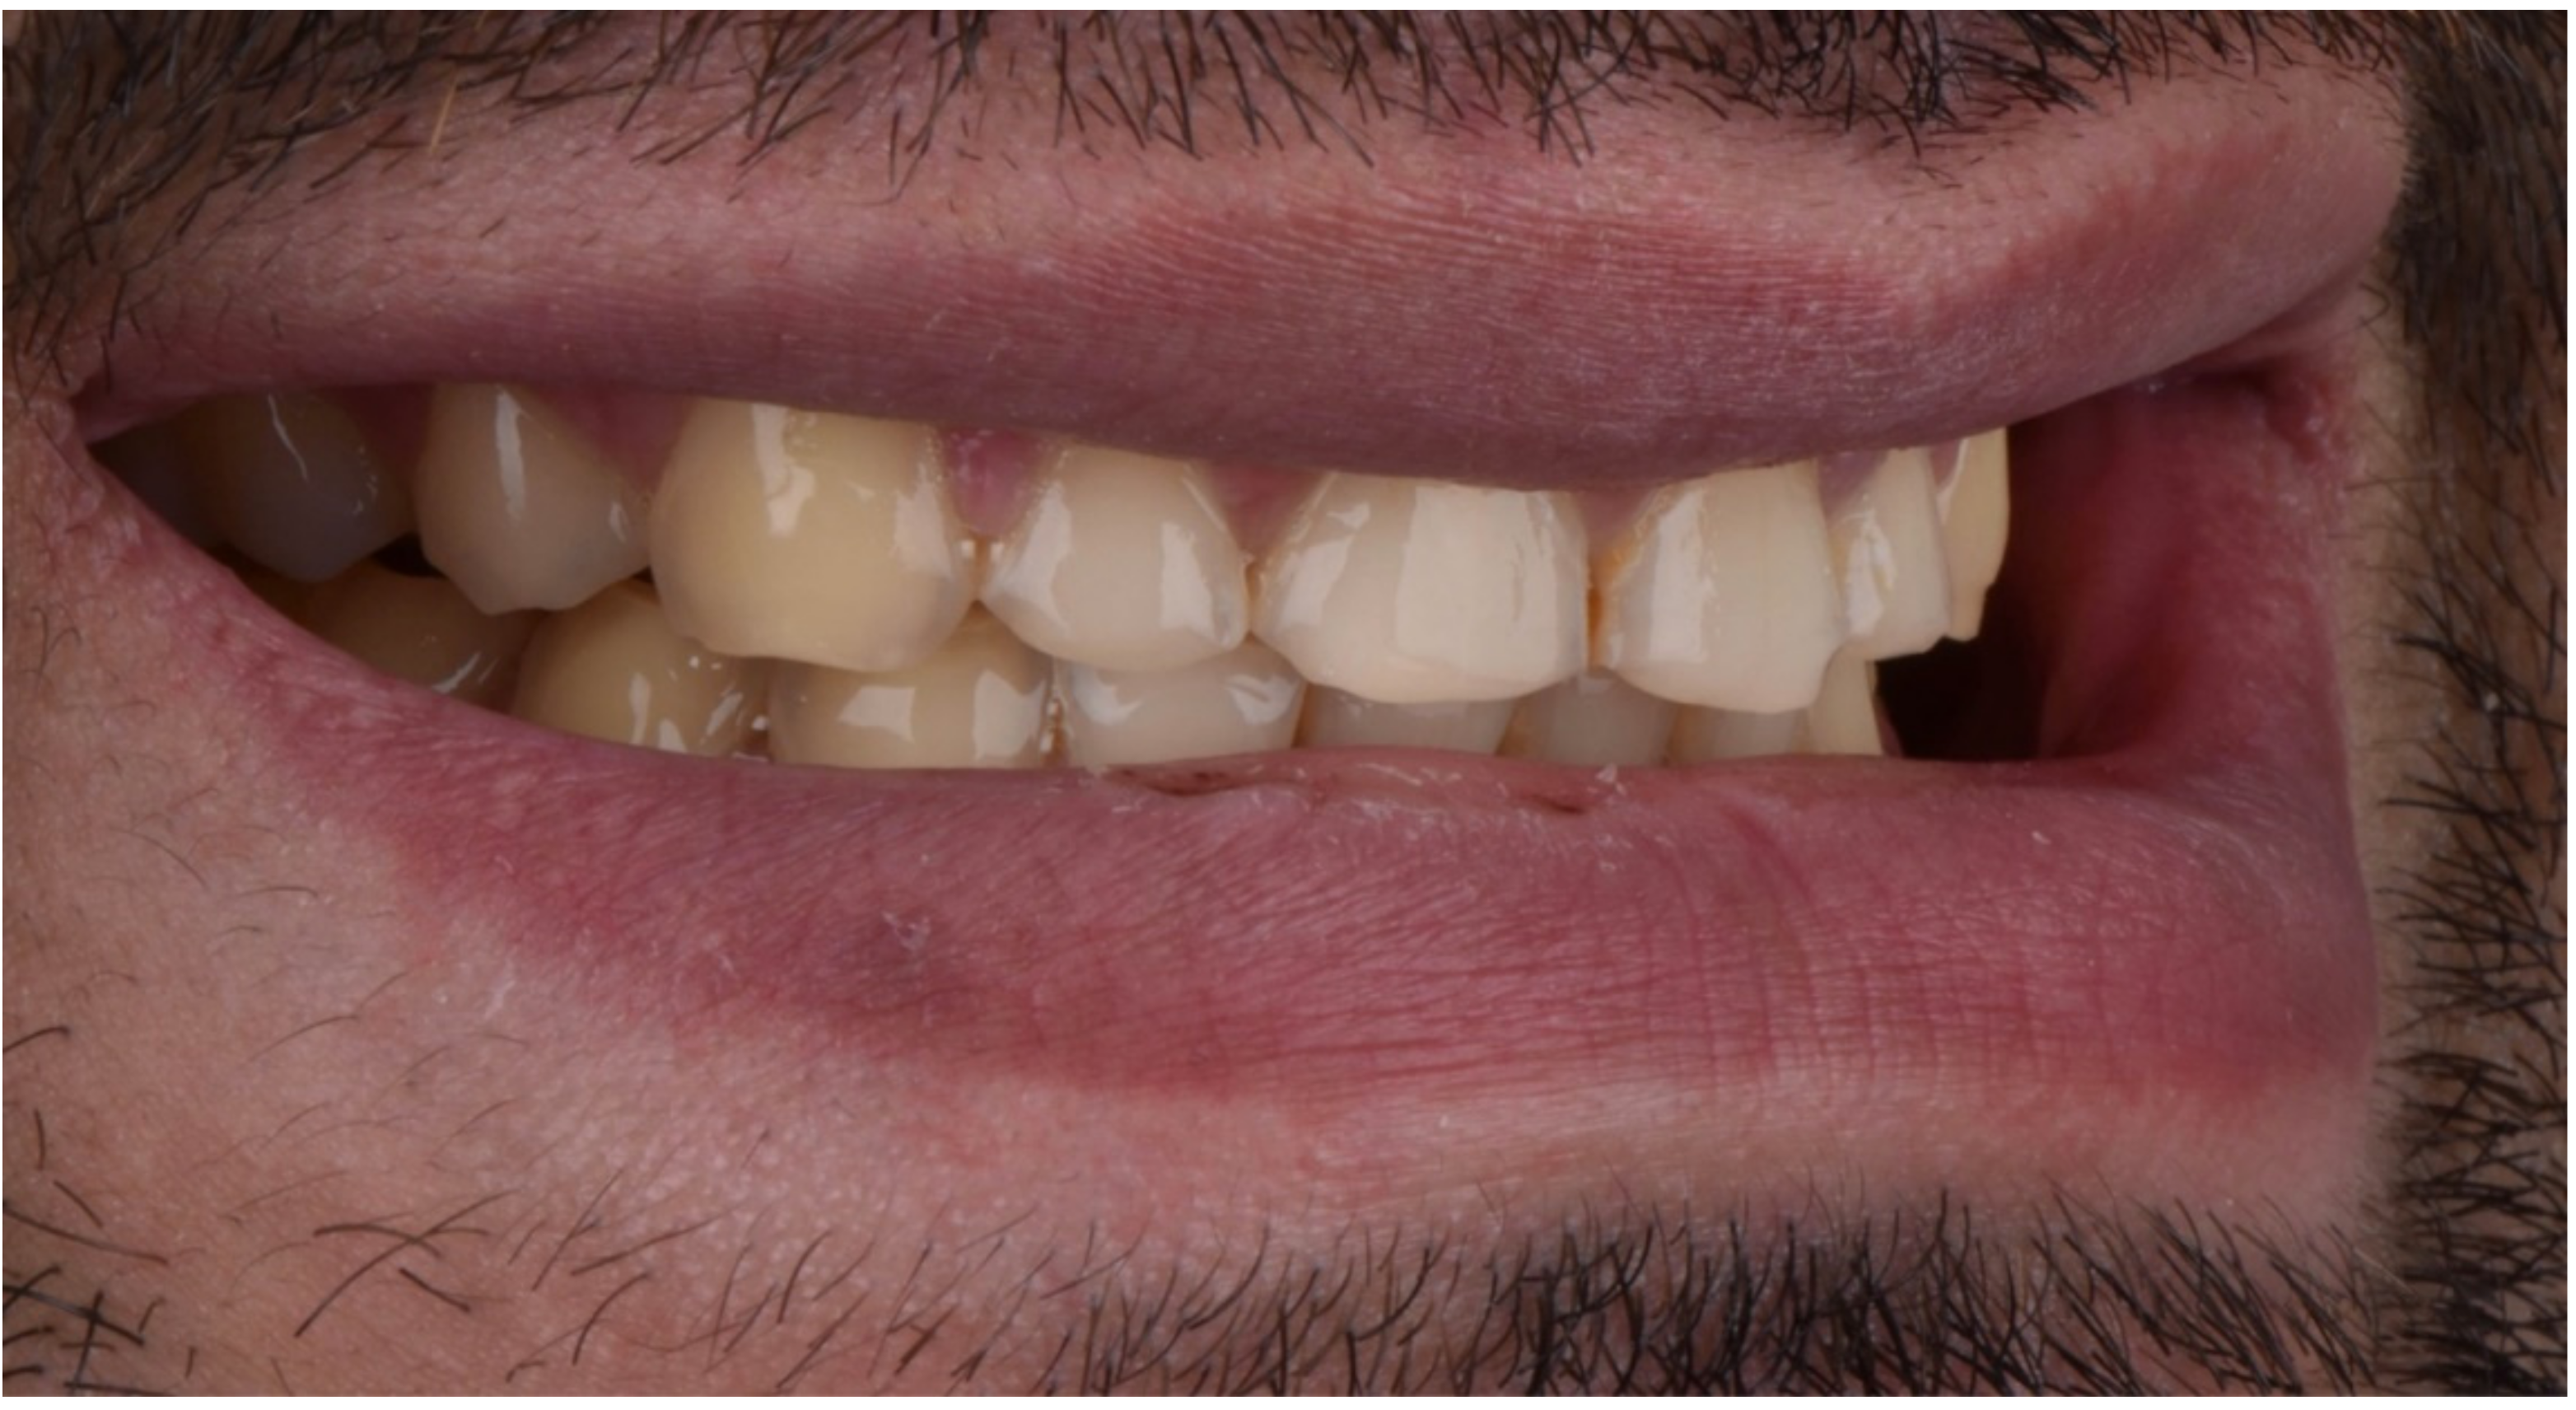

2. Clinical Report